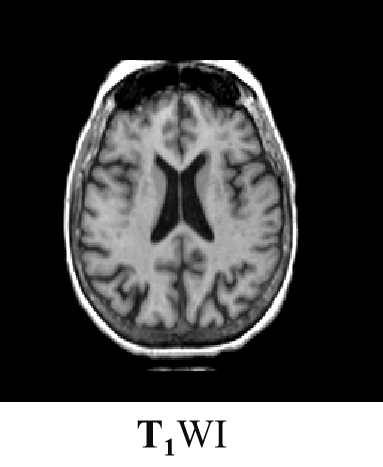

磁共振成像(Magnetic Resonance Imaging , MRI)是利用原子核在强磁场内发生核磁共振产生的信号经图像重建的成像技术。

磁共振成像过程中,射频脉冲激发后所记录到的信号强度的大小主要与以下因素有关:

一是生物组织本身的因素,包括T1、T2和质子密度等;

二是脉冲序列的形式。

T2加权:

PD加权: